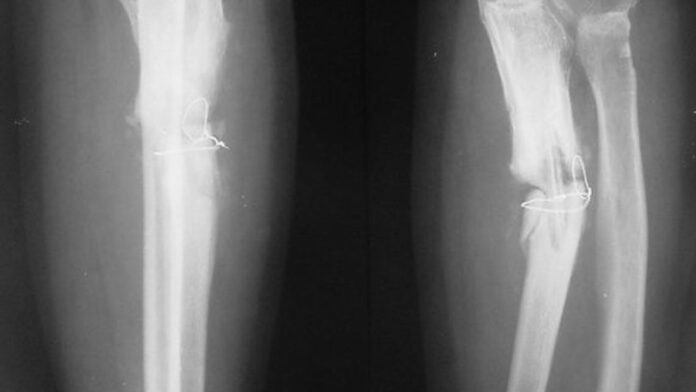

Cercetătorii chinezi susţin că au dezvoltat un adeziv osos care poate fi folosit pentru a trata fracturile şi fragmentele osoase zdrobite, printr-o procedură care durează doar trei minute.